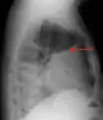

پلورال افیوژن از نمای جانبی در یک عکس رادیوگرافی قفسه سینه در بیماری که ایستادهاست.